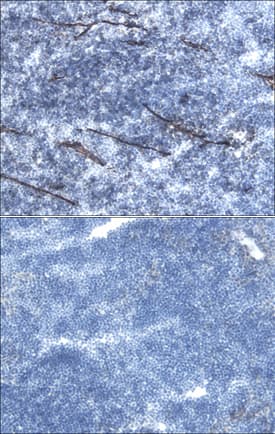

Bmp10 conditional deletion has no impact on tumor growth, angiogenesis and lung metastasis in the E0771 mammary cancer model. a Schematic representation of the experimental protocol for Bmp10 specific deletion and E0771 cells implantation. Tamoxifen was injected in all 3-week-old mice; 3 weeks later, E0771 cells were injected and tumor growth was analyzed for 3 weeks. b Plasmatic levels of BMP10 in control (CTL, n = 15) and Bmp10 conditional KO (Bmp10-cKO, n = 15) mice assessed by ELISA at the end of the experiment. c Tumor growth was assessed by caliper measurement every 2 to 3 days after tumor detection (CTL n = 7, Bmp10-cKO n = 8, 1 representative experiment out of 3). d Representative images of the tumors stained for podocalyxin (red), lectin (green) and cell nuclei (blue, Hoechst). Scale bar 50 μm. e Vascular density quantified by podocalyxin surface area (% of tumor area) and (f) Quantification of vessel perfusion by lectin staining (% area of lectin/podocalyxin) (CTL n = 7, Bmp10-cKO n = 8, 1 representative experiment out of 3). g Total area, (h) number and (i) mean size of lung metastases per mice bearing metastases (CTL n = 10, Bmp10-cKO n = 9, 2 experiments). c Data are the mean ± SEM. Statistical analysis: Two-way matched ANOVA. b, e, f, g, h, i Data are the median ± interquartile range. Statistical analysis: Mann-Whitney test. ****p ≤ 0.001 significantly different Image collected and cropped by CiteAb from the following publication (https://pubmed.ncbi.nlm.nih.gov/30165893), licensed under a CC-BY license. Not internally tested by R&D Systems.